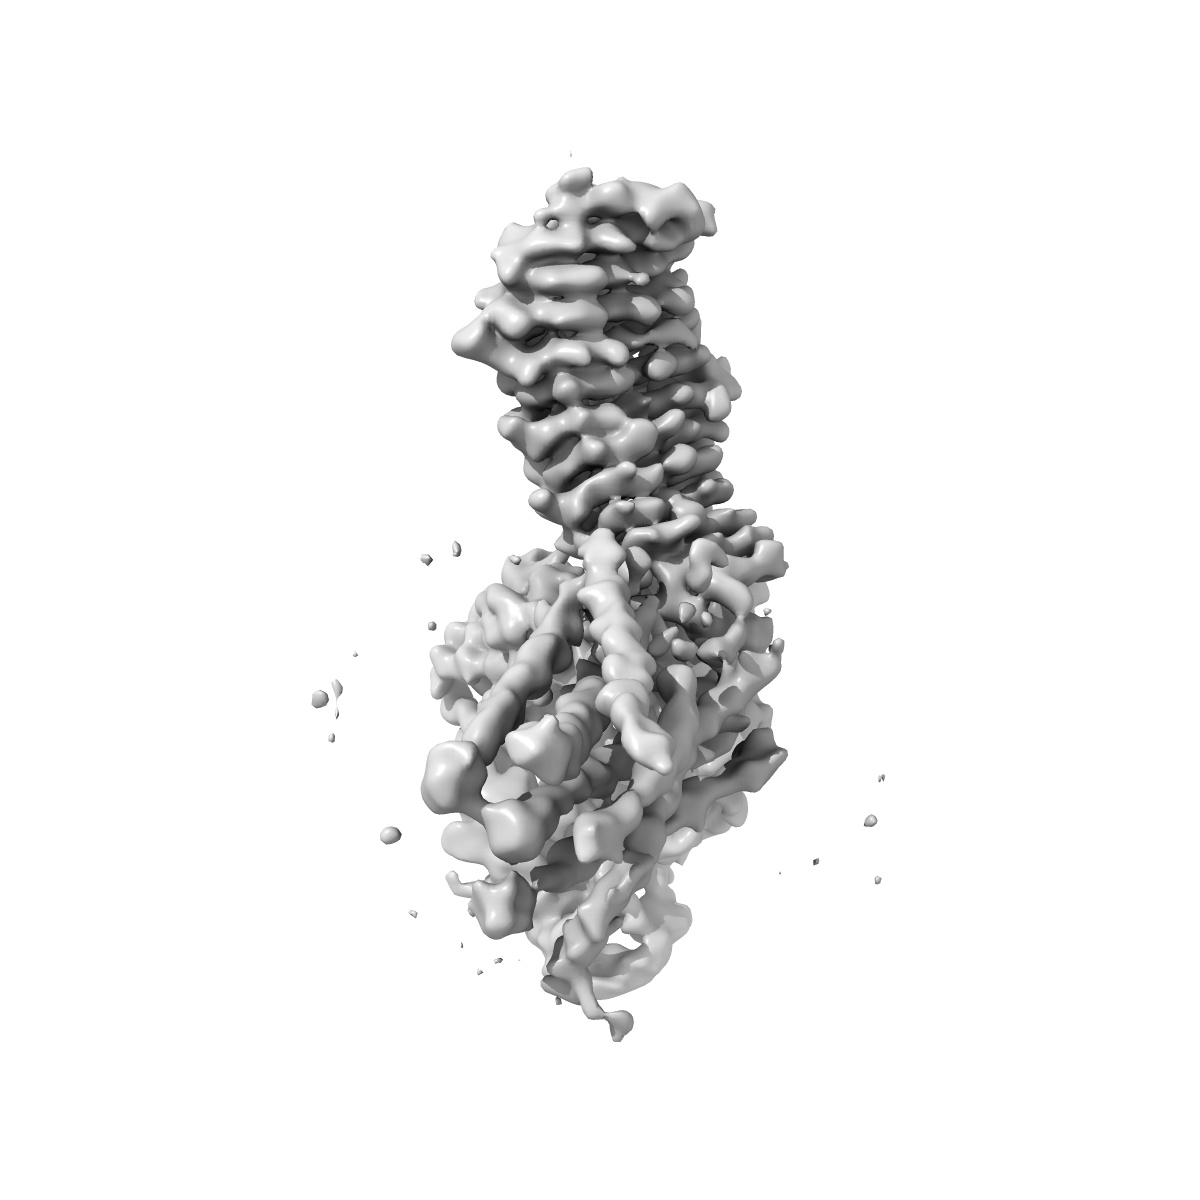

Human Thyrotropin receptor bound by CS-17 Inverse Agonist Fab/Org 274179-0 Antagonist

Single-particle3.1 Å

Sample: Human Thyrotropin receptor in complex with the murine inverse agonist Fab fragment CS-17